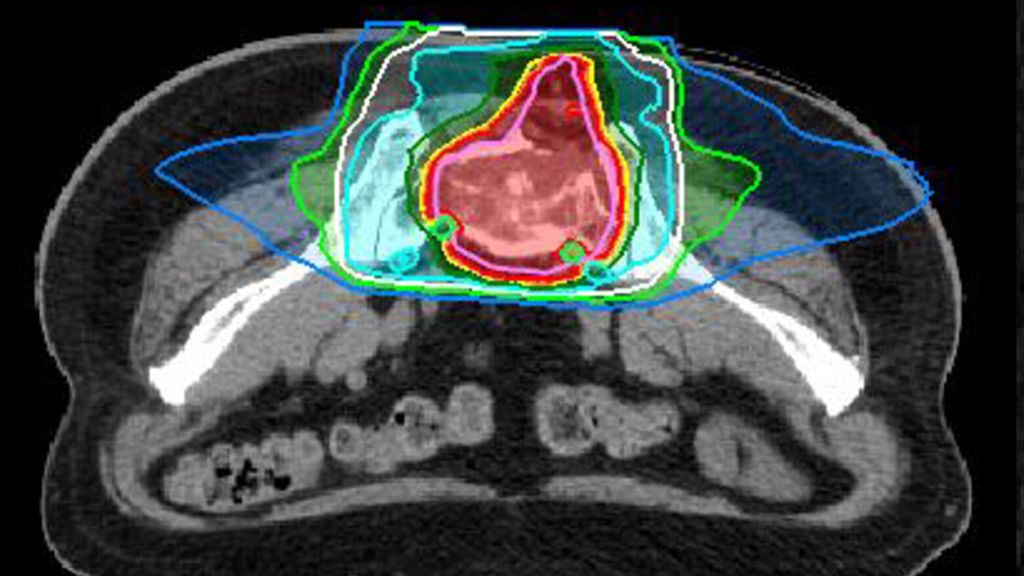

MedAustron behandelt nationale und internationale Patient*innen. Eine Therapieanfrage kann durch Fachkolleg*innen oder durch Patient*innen selbst erfolgen. Die Indikation zur Behandlung wird durch ein interdisziplinäres Tumorboard geprüft. Die Behandlungskosten trägt die Gesundheitsversicherung. Nach Bestätigung der Indikation und der Behandlungskostenübernahme wird mit der Behandlungsplanung begonnen. Voraussetzung dafür ist ein ausführliches ärztliches Aufklärungsgespräch. Danach werden individuelle Positionierungen, eine Planungs-Computertomografie und -Magnetresonanztomografie durchgeführt. Diese sind für die Bestrahlungstarget-Definition und die Berechnung des Bestrahlungsplans essenziell. Ein Beispiel für einen solchen Behandlungsplan ist in Abbildung 2 zu sehen.

Abb. 2: Planbeispiel einer definitiven Behandlung eines Chordoms des Sakrums mit 16 Fraktionen à 4,6 Gy RBE pro Fraktion bis zu einer Gesamtdosis von 73,6 Gy RBE mit Kohlenstoffionen

Die Behandlung selbst wird in mehreren Fraktionen (Einzelbehandlungen) durchgeführt. Die Anzahl ist von der Partikelart und der Tumorlokalisation abhängig. Kohlenstoffionen werden üblicherweise in 16 oder 22 Fraktionen appliziert, Protonen in 22 oder mehr Fraktionen, abhängig davon, ob es sich um reine postoperative Behandlung handelt oder ob ein Tumorrest besteht. Die Reduktion der Fraktionsanzahl hat auch logistische Vorteile, weil dadurch die Gesamtdauer der Behandlung verkürzt werden kann.